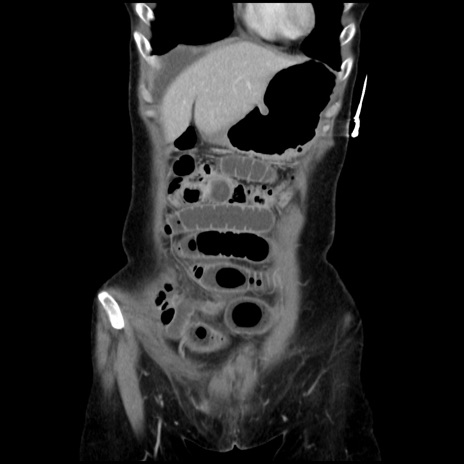

横断像

【症例】40歳代 女性

【主訴】上腹部痛、嘔気・嘔吐

【現病歴】約9時間前頃から急に上腹部痛、嘔気、嘔吐が出現。改善しないため救急要請。

【既往歴】子宮頚癌(広汎子宮全摘術、放射線療法)、腸閉塞

【身体所見】腹部:平坦、軟、腸雑音亢進、上腹部を中心に腹部全体に圧痛あり。

【データ】WBC 8400、CRP 0.03